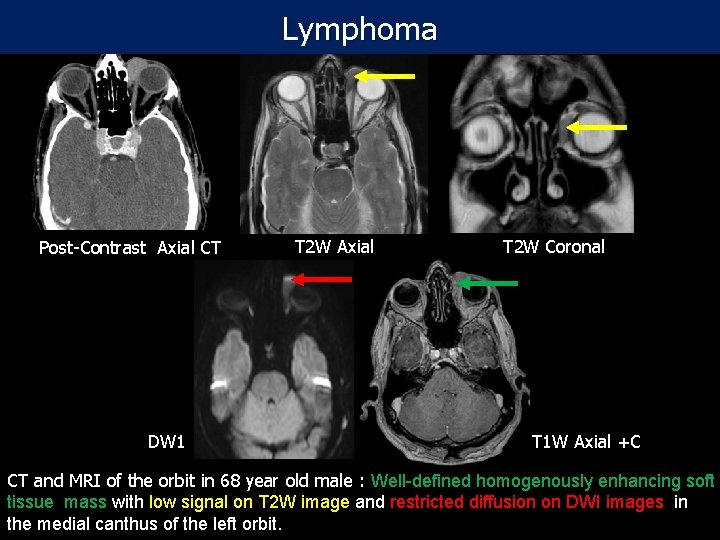

Lymphoma Post-Contrast Axial CT DW 1 T 2 W Axial T 2 W Coronal T 1 W Axial +C CT and MRI of the orbit in 68 year old male : Well-defined homogenously enhancing soft tissue mass with low signal on T 2 W image and restricted diffusion on DWI images in the medial canthus of the left orbit.